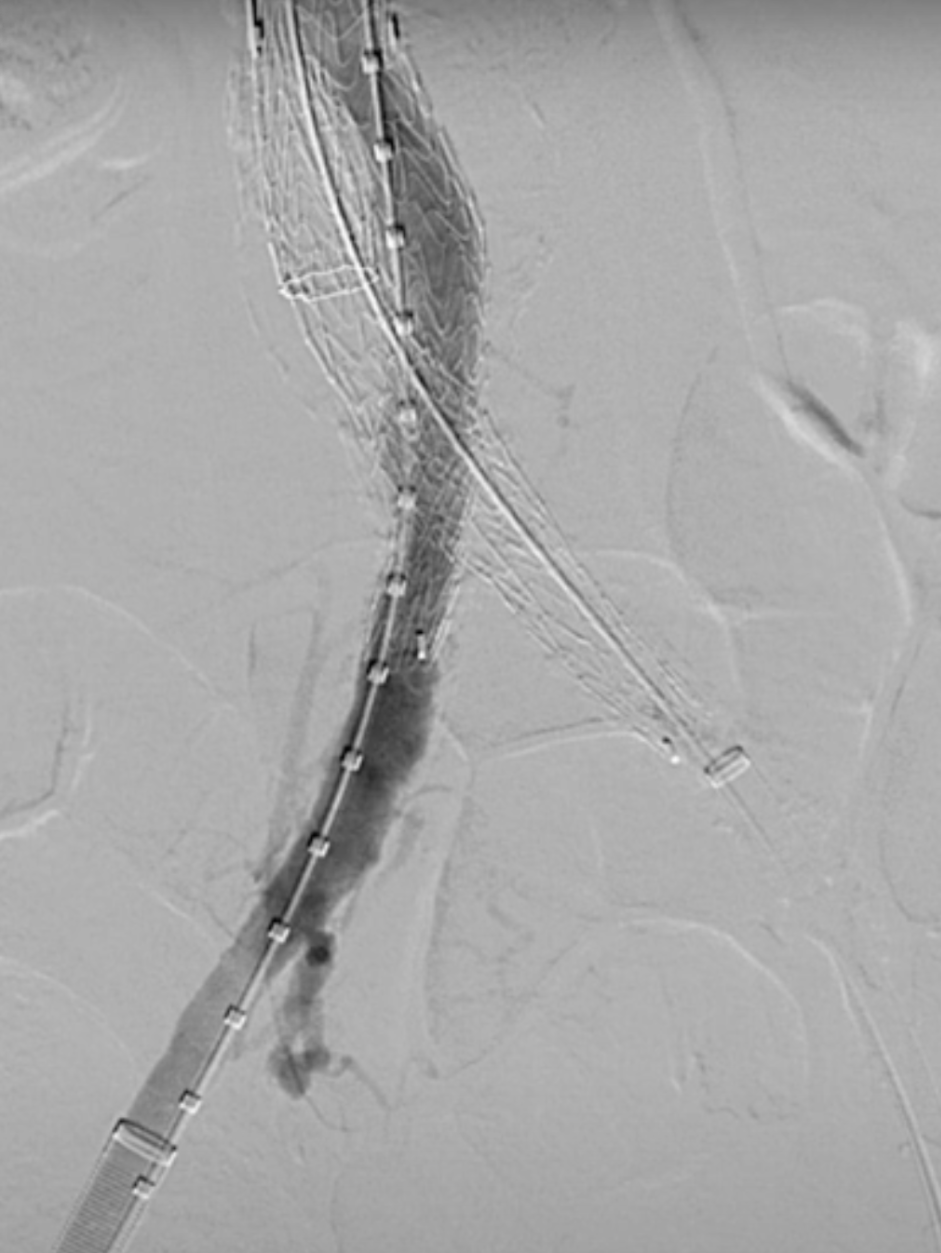

在植入主动脉支架后,首先开通SMA,配合可调弯导管调整激光导管角度,多角度视图下确保对准。发射激光(60-60mJ/mm2),激光穿透主体支架覆膜后立即推进导丝。

确认导丝进入靶血管后移除激光导管,依次使用4mm快交球囊、5mm切割球囊进行扩张开窗,交换入35系统导丝,在预植入的支架内引入VBX球扩覆膜支架,远端超过预植入支架远端,近端伸入主动脉3-5毫米,扩张球囊使VBX释放。

再次扩张VBX支架近端使其锚定于主动脉支架上。

造影确认开窗支架的通畅性。

在激光开窗前多角度确认。